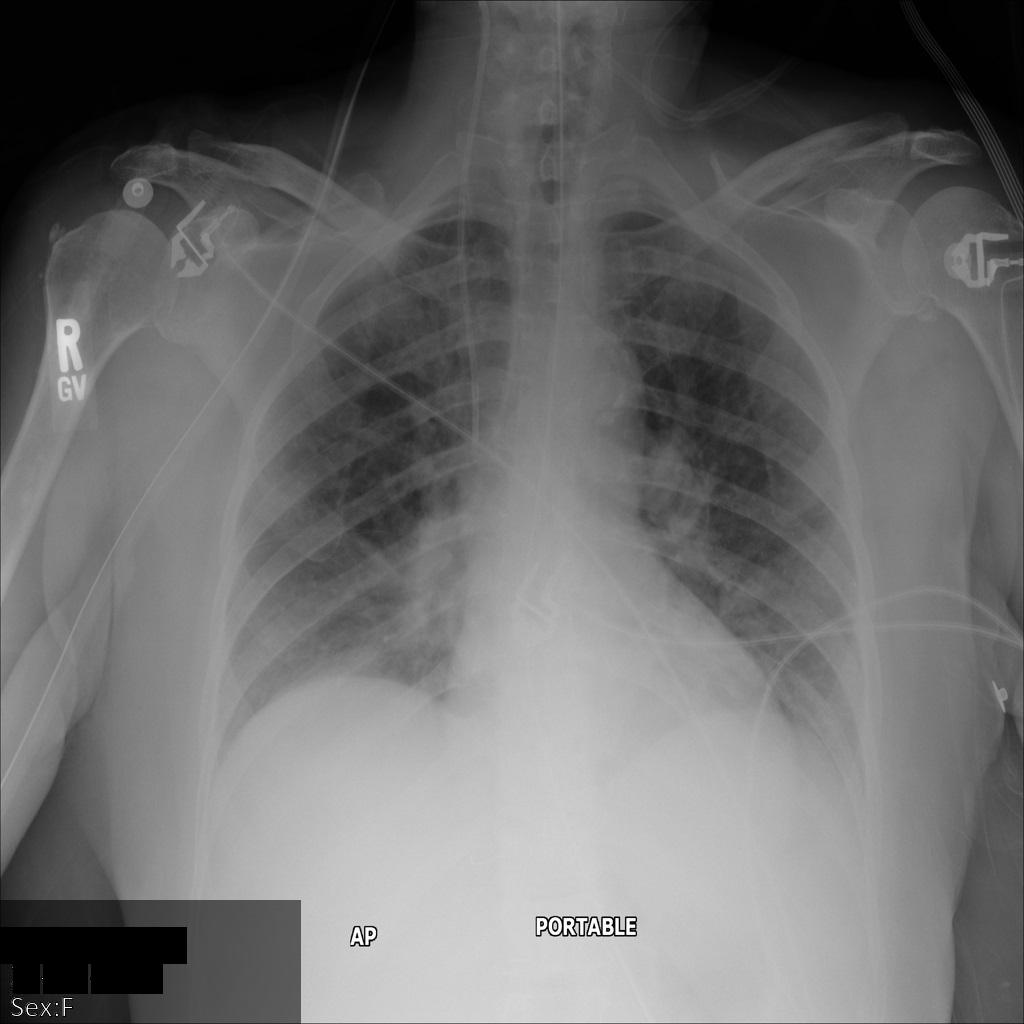

画像にある焼き付き機密テキストのみを秘匿化する

次のサンプルは、データセット内の DICOM 画像にある焼き付き機密テキストを秘匿化する方法を示しています。そのためには、TextRedactionMode フィールドに REDACT_SENSITIVE_TEXT を指定します。

REDACT_SENSITIVE_TEXT を指定すると、デフォルトの DICOM infoTypes で指定された infoType が秘匿化されます。次の秘匿化のために、2 つの追加のカスタム infoType も適用されます。

- カルテ番号(MRN)などの患者 ID

- 登録番号

次の画像は、患者の X 線を秘匿化していない状態を示しています。

REDACT_SENSITIVE_TEXT オプションを使用して Cloud Healthcare API に画像を送信すると、画像は次のように表示されます。

次のことを確認できます。

- 画像の左下にある

PERSON_NAMEが秘匿化された - 画像の左下にある

DATEが秘匿化された

患者の性別は、デフォルトの DICOM infoTypes に従って機密テキストと見なされないため、秘匿化されませんでした。